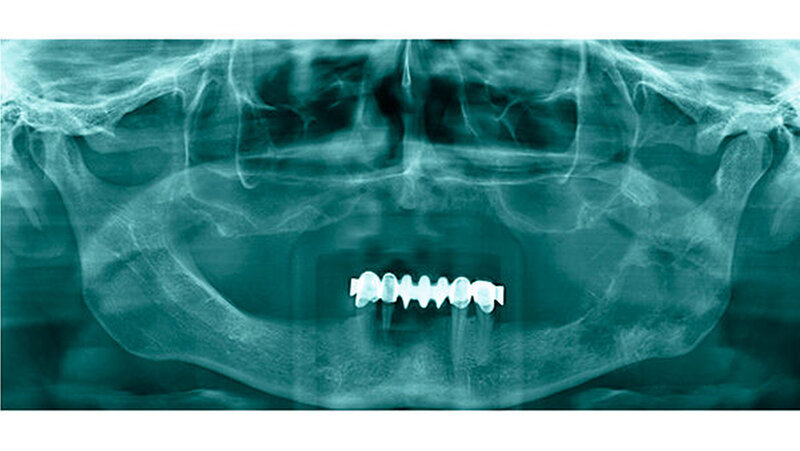

Klinisch präsentierte sich eine Auftreibung des Unterkiefers links mit Ulzeration im dritten Quadranten (Abbildung 2) bei einer auffälligen Anästhesie der linken Unterlippe. Tastbare Lymphknoten lagen nicht vor. In der Panoramaschichtaufnahme (Abbildung 3) zeigten sich linksseitig größtenteils osteolytische, partiell sklerotische Areale mit einem verplumpten Processus coronoideus. Hinweisgebend auf eine mögliche Diagnose waren schließlich die crestal gelegenen Spikulae. Eine alio loco bereits durchgeführte Probeexzision sicherte ein chondroblastisch differenziertes Sarkom.

Mit dieser Diagnose wurde die Patientin zur weiteren Therapie in die Mund-, Kiefer-, Gesichtschirurgie der Universitätsmedizin Mainz überwiesen, in der das Staging mittels Computertomografie der Kopf-/Hals-Region sowie des Thorax/Abdomen komplettiert wurde. Hierin zeigte sich lokal eine Ausbreitung bis an den Processus condylaris mit bereits bestehendem Kontakt zum Sinus maxillaris (Abbildungen 4 und 5). Bei pulmonalen Verdichtungen konnte eine Metastasierung nicht sicher ausgeschlossen werden, eine abdominelle Absiedlung bestand nicht.